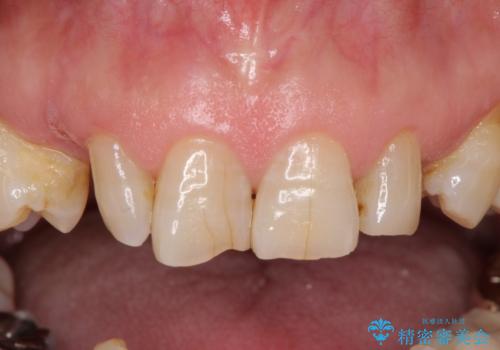

乳歯や矮小歯の多い前歯 部分矯正と補綴治療による審美歯科治療

- 乳歯や矮小歯が多くある前歯部の審美障害が気にして来院された患者様です。

上顎の矮小歯は隙間が多く、歯軸の傾斜も大きかったため、部分矯正により補綴治療前に歯の位置を整えることとしました。

下顎の乳歯は支台歯として機能することは困難と思われたので、事前に抜歯をし、上顎の矯正治療終了のタイミングに合わせて、セラミックブリッジにて補綴治療することとしました。

- 治療費の目安: 140万円(税込)費用は治療当時の料金となります